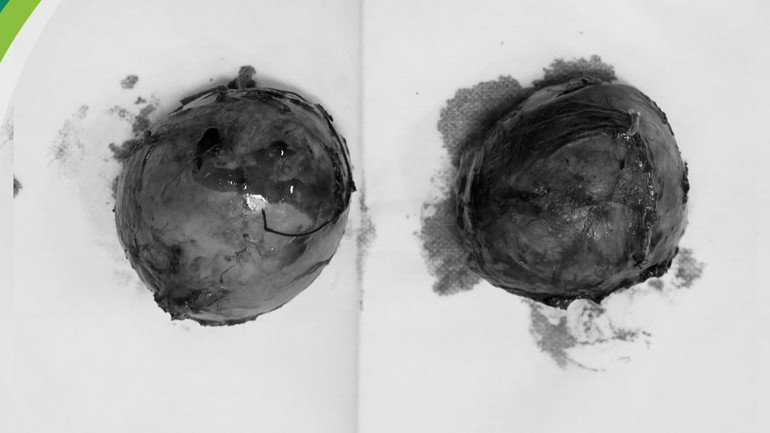

Bác sĩ chuyên khoa II Vũ Mạnh Hoàn, Trưởng khoa Ngoại Gan-Mật-Tuỵ, Phó Giám đốc Trung tâm Ngoại Tổng hợp chia sẻ: "Bệnh nhi được phẫu thuật nội soi nhằm giảm tối đa tổn thương, chúng tôi cắt hoàn toàn 2 khối u tuyến thượng thận. Song song với đó, cố gắng giữ lại một phần tuyến thượng thận bên phải. Trong khi mổ, các bác sĩ luôn hết sức thận trọng và tỉ mỉ từng thao tác, vì việc chạm vào khối u, rất dễ gây ra cơn tăng huyết áp kịch phát dẫn tới xuất huyết não, suy tim cấp, nhồi máu cơ tim”.

| Khối u tuyến thượng thận được loại bỏ. |